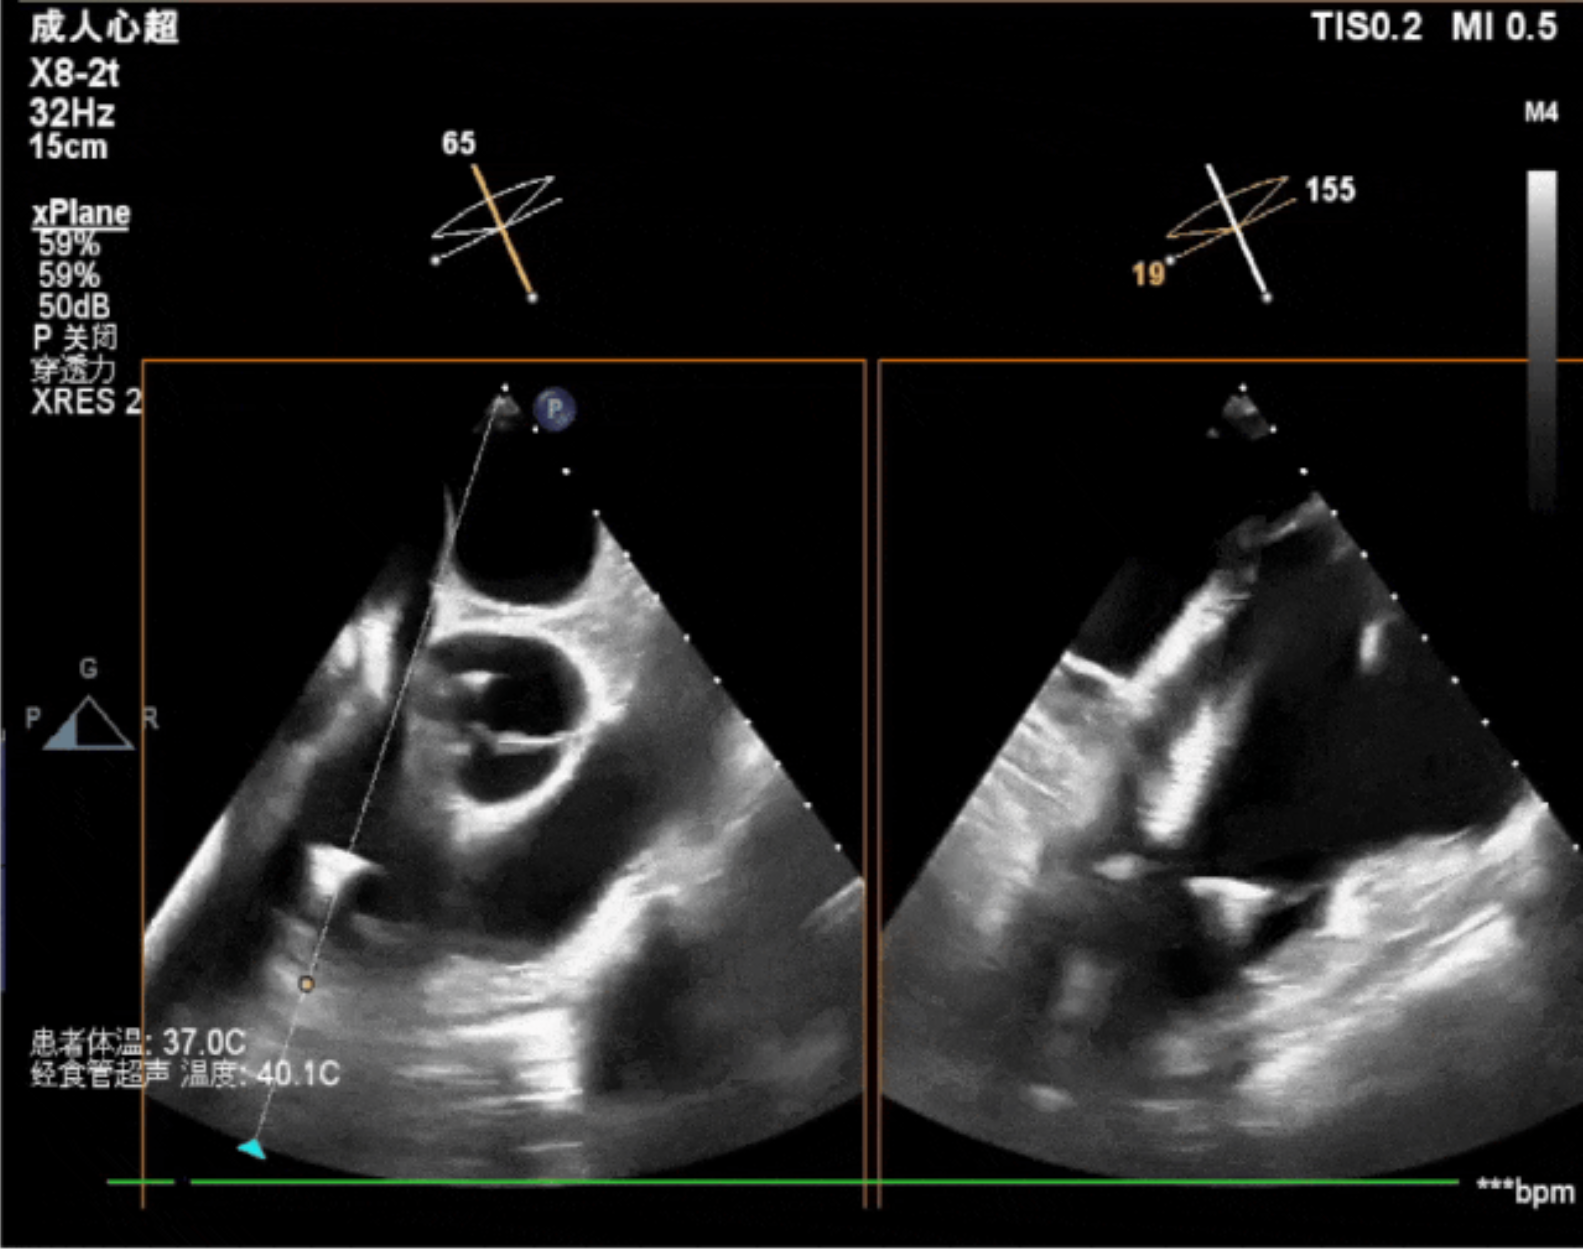

術(shù)中影像

術(shù)中經(jīng)食道超聲輔助下可見LuX-Valve Plus夾持件抓捕瓣葉狀態(tài)良好,夾持件在位,室間隔錨定位置良好,假體瓣膜整體錨定狀態(tài)穩(wěn)固。

術(shù)后即刻經(jīng)食道超聲可見,三尖瓣假體瓣膜位置合適,牛心包瓣葉運動狀態(tài)良好,開閉正常,瓣周及瓣葉對合緣處未見明顯返流,心電圖及心包狀態(tài)較術(shù)前無明顯變化。

本次直播手術(shù)中,手術(shù)團(tuán)隊在超聲與DSA等多維影像手段的支持下,精準(zhǔn)嫻熟的完成LuX-Valve Plus瓣膜的植入,器械操作時間僅為30分鐘,瓣膜植入后術(shù)中即刻三尖瓣返流消失,多普勒超聲下無明顯瓣周漏或中心性返流,肺動脈壓正常,平均跨瓣壓差僅為1mmHg,人工瓣膜運動正常,術(shù)后1小時內(nèi)該患者即安返病房。